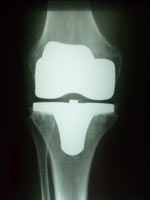

• Endoprothetik

• Verschleiß der Gelenkflächen kann zu einer schmerzhaften Einsteifung, Fehlstellung oder Instabilität des Kniegelenkes führen. Moderne Prothesen ersetzen ein, zwei oder alle drei Gelenkanteile (die Innenseite, die Kniescheibe und ihr Gleitlager, die Außenseite). Die Prothesenteile sind ungekoppelt oder – bei Vorliegen einer Instabilität – achsgeführt und zumeist zementiert.

• Durch Knochenerweichung (Osteoporose), Entzündung, Knochenbruch oder andere Ursachen kann eine Prothesenlockerung auftreten. Dann werden einzelne Komponenten oder die ganze Prothese gewechselt. Zum Einsatz kommen Standard- oder Spezialprothesen. Beim Protheseninfekt kann auch eine Interimsprothese aus Antibiotika-beladenem Knochenzement für einige Wochen eingesetzt werden.

Zweidrittelprothese Zweidrittelprothese Oberflächenprothese Oberflächenprothese